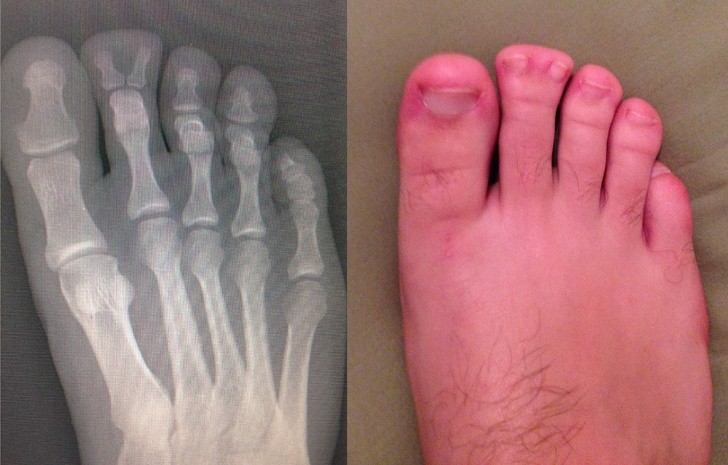

Ljudje smo resnično čudna bitja in se nam lahko zgodijo neverjetno bizarne stvari. Ti rentgenski posnetki bodo šokirali tudi tiste, ki mislijo, da so videli že vse.

Rentgen je eden najboljših izumov človeštva in v nekaterih situacijah je nepogrešljiv. Še posebej zato, ker se velikokrat zgodi, da ljudje, še posebno otroci, požirajo predmete, ki niso del dnevne prehrane. Da ne omenjamo psov, ki poskušajo prežvečiti vse, kar vidijo, in tako velikokrat pogoltnejo neprimerne stvari.

Radiologi so tako že precej navajeni, da na rentgenskih posnetkih vidijo čudne stvari in nekatere izmed teh, ki smo jih za vas zbrali v galeriji, jih sploh niso presenetile. Tukaj je 15+ odštekanih in na trenutke šokantnih rentgenskih posnetkov.